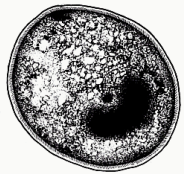

Blastocystis hominis (cyst)